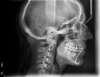

Rédicive d'un traitement dans l'enfance repris avec des gouttières

A-Début